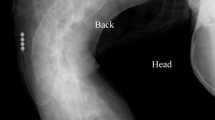

Novak, P. Physics: F-SW and R-SW. Basic information on focused and radial shock wave physics. In Multidisciplinary Medical Applications. (eds. Lohrer, H. & Gerdesmeyer, L.) 28–49 (Level 10 Buchverlag Daniela Bamberg, 2015).

Ogden, J. A., Tóth-Kischkat, A. & Schultheiss, R. Principles of shock wave therapy. Clin. Orthop. Relat. Res. https://doi.org/10.1097/00003086-200106000-00003 (2001).